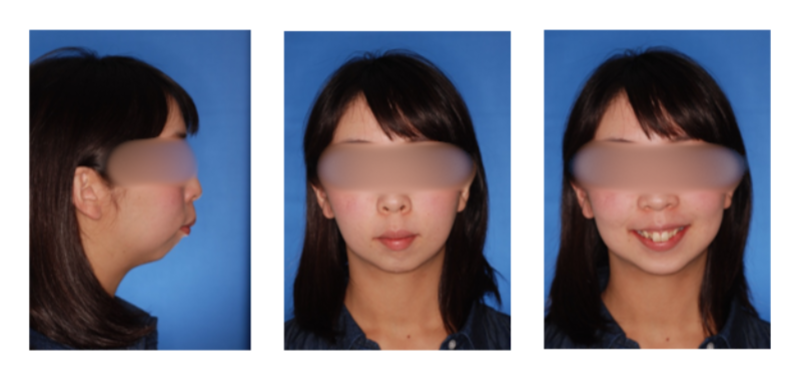

外科症例(反対咬合)の症例

初診時

治療終了時

治療終了から3年経過時

(保定開始から3年経過時)

初診

治療終了時

治療終了後から3年経過時

(保定開始時から3年経過時)

| 年齢・性別 |

20代 女性 |

| 主訴 |

咬み合わせが逆なのが気になる。 |

| 治療について |

骨格的な問題が大きいことから外科的矯正治療としました。 |

| 注意点・リスク |

矯正治療中に顎の位置が不安定になり易く顎関節症を発症する可能性が高くなります。また、歯牙移動に伴う痛み、発音し難くなったり、咬み難さが生じることがあります。歯根吸収(歯の根が短くなる状態)、歯髄壊死(歯の神経が失活した状態)、歯肉退縮(歯茎が下がる状態)、骨性癒着(骨と歯が癒着し、歯が動かない状態)が起きる可能性があります。外科手術を行うため、術後に知覚麻痺、鈍麻が起こる可能性があります。大量出血の可能性もあるため術前に自己血貯血をしておきます。 |

| 治療期間 |

2年9ヶ月 |

| 治療費用 |

累計約550,000円(保険適用の治療になります。 手術費用も含んだ総額です。) |

| 治療に用いた主な装置 |

マルチブラケット装置(表側の装置)、歯科矯正用アンカースクリュー、パラタルレバーアームシステム |

| 抜歯部位 |

上顎左側第二小臼歯、右側第一小臼歯、両側第二大臼歯、下顎両側第三大臼歯を抜歯 |

| 通院回数 | 26回 |